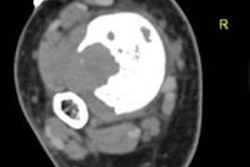

The most common sites for metastases were in the pelvis and spine, and there were no other metastases outside of those locations, the researchers found. The patient-based analysis revealed that 16 (33%) of the 49 patients had at least one metastasis found by one of the three imaging modalities. Only five patients (9%) had skeletal metastases that were verified by both DWI-MRI and NaF-PET/CT.

Of those five patients, two had widespread bone metastases and died eight and 16 months after the initial imaging. The other three subjects showed partial regression on follow-up studies.

| Numerous bone metastases were detected in a 67-year-old man with prostate cancer. Bone scintigraphy (left) and NaF-PET/CT (right) images show more lesions in skull and ribs than whole-body bone MRI. Images courtesy of the American Journal of Roentgenology. |